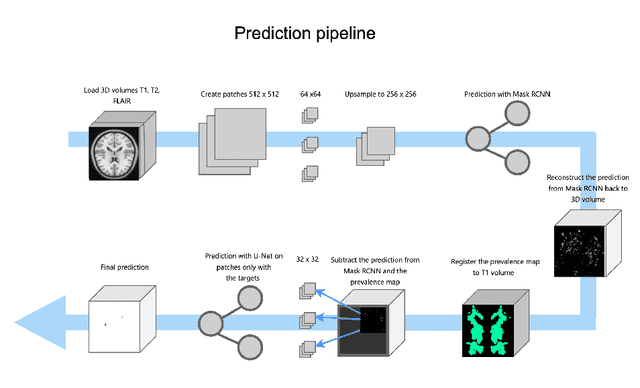

Lacunes of presumed vascular origin are fluid-filled cavities of between 3 - 15 mm in diameter, visible on T1 and FLAIR brain MRI. Quantification of lacunes relies on manual annotation or semi-automatic / interactive approaches; and almost no automatic methods exist for this task. In this work, we present a two-stage approach to segment lacunes of presumed vascular origin: (1) detection with Mask R-CNN followed by (2) segmentation with a U-Net CNN. Data originates from Task 3 of the "Where is VALDO?" challenge and consists of 40 training subjects. We report the mean DICE on the training set of 0.83 and on the validation set of 0.84. Source code is available at: https://github.com/hjkuijf/MixLacune . The docker container hjkuijf/mixlacune can be pulled from https://hub.docker.com/r/hjkuijf/mixlacune .